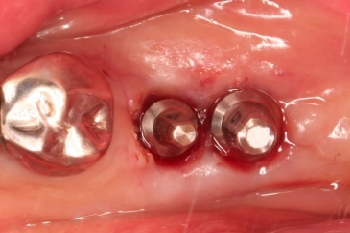

千葉市中央区 N.I様 右下67番 インプラント上部構造

担当歯科医師:佐藤英司